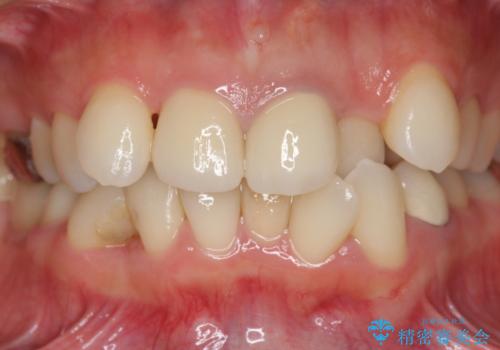

著しいがたつきによる清掃困難 歯牙抜去とセラミック治療

- 前歯の変色の改善を希望され来院されました。

X線写真より、充填剤の突き出た状態の根管治療の再治療を行い、セラミック治療を計画すると同時に、

歯ブラシがしづらく虫歯の原因となっている歯の位置の悪い右上側切歯の抜去を行います。

- 26.4万円(ジルコニアクラウン×2・仮歯×2)費用は治療当時の料金となります

清掃を難しくしている歯を抜去することで虫歯の再発を防ぐような治療方針としました。